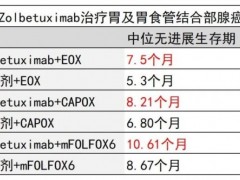

胃癌靶向治疗 2023-09-22

胃癌靶向治疗 2023-09-22

胃癌靶向治疗 2023-08-31

胃癌靶向治疗 2023-08-31